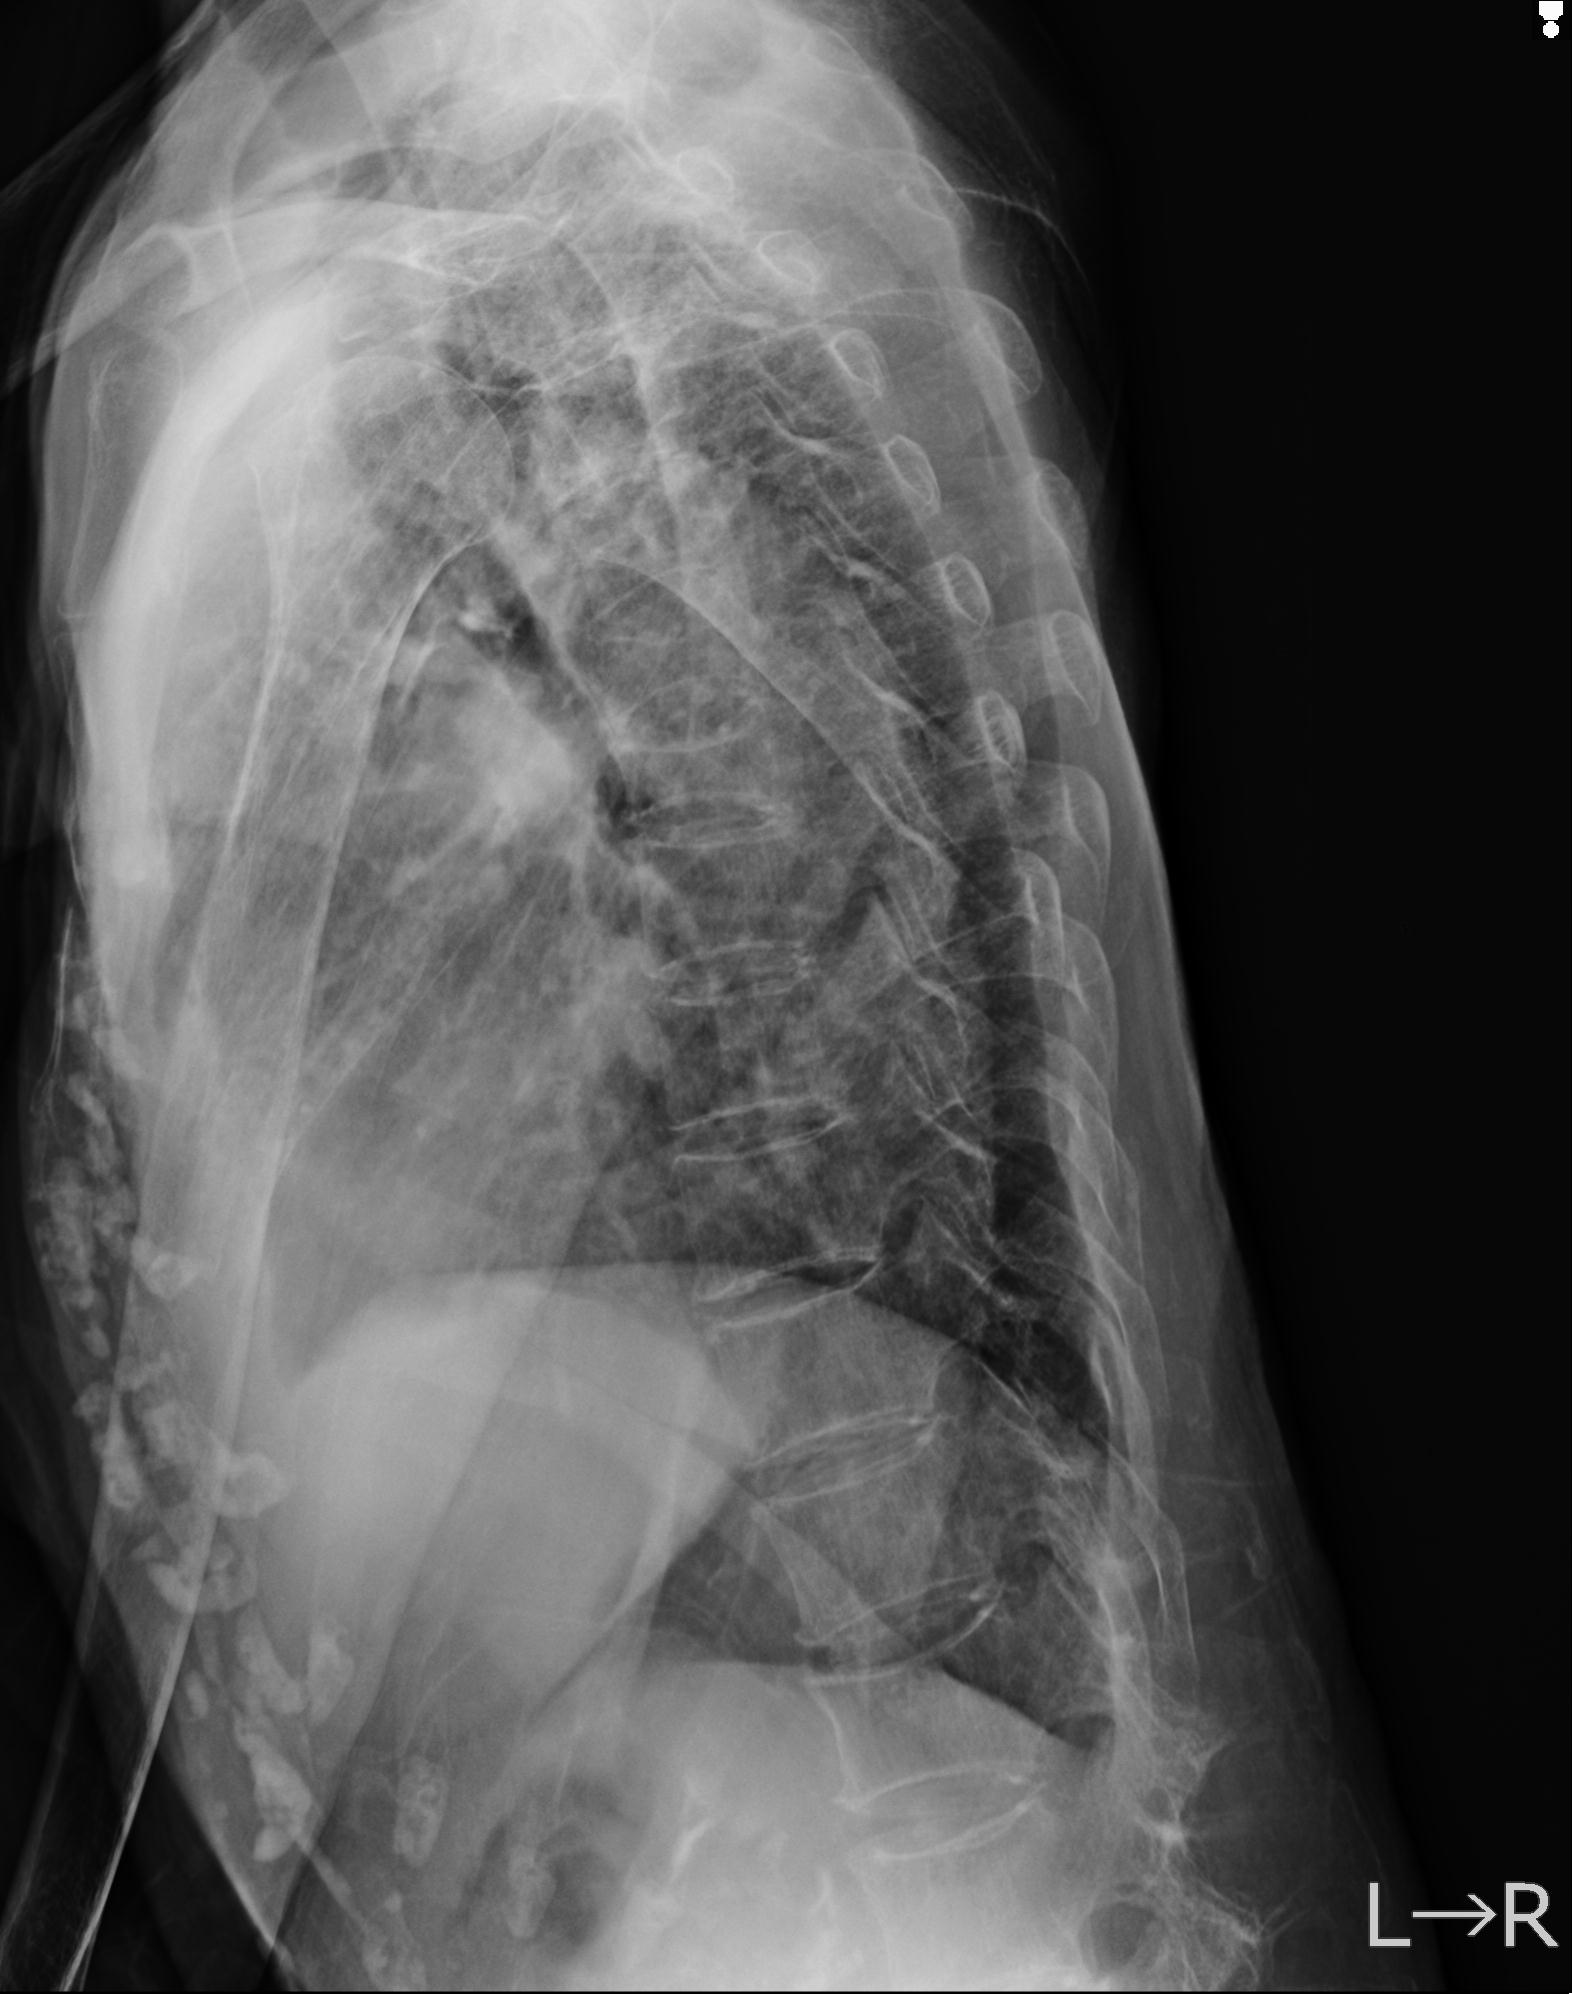

症例写真集